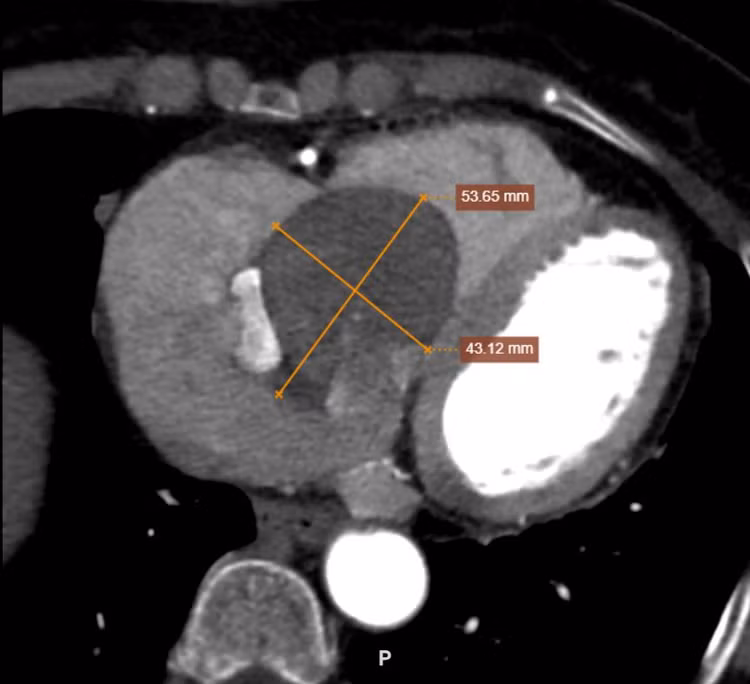

Tại Bệnh viện Đa khoa tỉnh Phú Thọ, sau khi thực hiện các xét nghiệm, siêu âm tim và chụp cắt lớp vi tính (CT), các bác sĩ xác định người bệnh có một khối u nhầy khổng lồ kích thước 53×43 mm nằm trong nhĩ phải, nguy cơ gây biến chứng nguy hiểm đến tính mạng.

Khối u khổng lồ qua phim chụp CT - Ảnh BVCC |

Khối u khổng lồ qua phim chụp CT - Ảnh BVCC